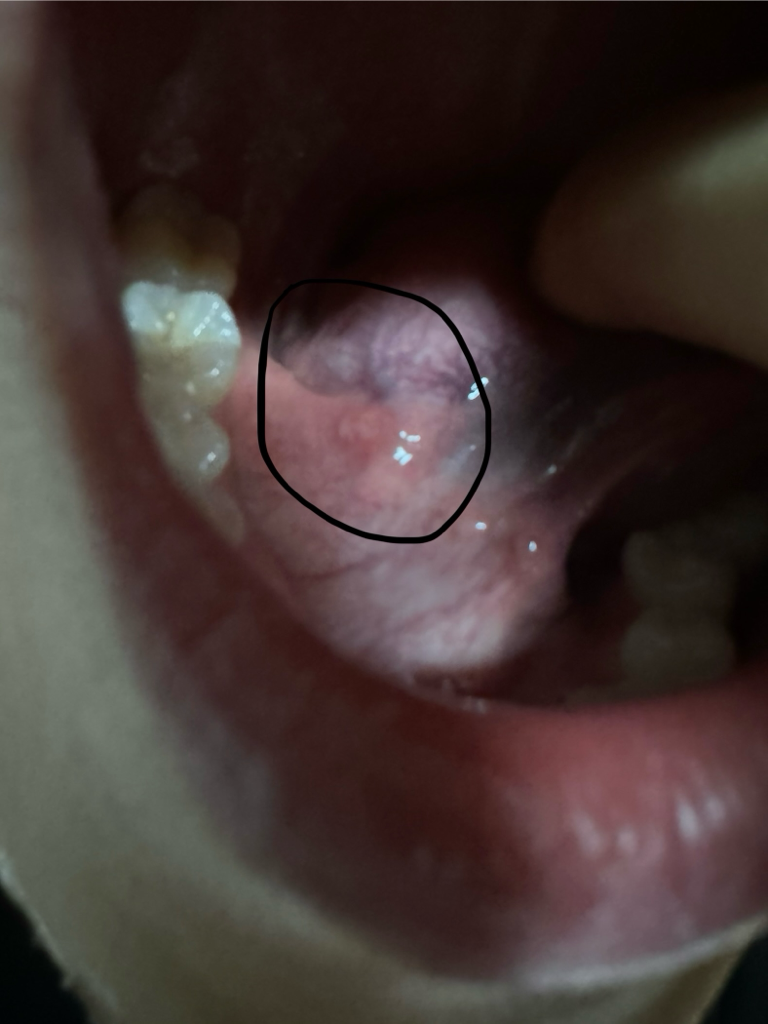

혀 밑에 통증이 자꾸 느껴져서 봤더니 흰색 염증이 있어요.

사진보시면 흰색 염증같은 거 있는 곳에 통증이 있어요.

동그라미 쳐놓은거는 알보칠바르기전이고 동그라미 없는거는 알보칠을 바른 후 입니다

• 3번 째 사진